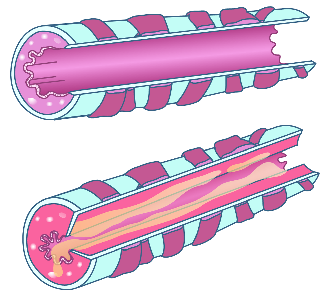

Detailreiche Fotografien aus der medizinischen Praxis ergänzen die Texte; moderne, genaue,

wissenschaftliche Zeichnungen geben Einblick in die Anatomie und die Funktion der Lunge und

anderer Organe.